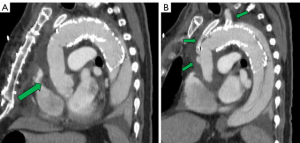

Cooling was initiated to a goal blood temperature of 18–20 °C, and the head was packed in ice. BIS monitor was used to confirm adequate cooling. The aorta was cross-clamped and antegrade and retrograde cardioplegia was given to arrest the heart. The aorta was transected at the level of the sinotubular junction. His aortic root was moderately dilated with annuloaortic ectasia. The aortic valve had some degenerative changes along the stress zones of the right and non-coronary cusps with fenestrations but the rest of the leaflets looked good. A decision was made to proceed with a valve-sparing aortic root reimplantation. Both coronary buttons were isolated and mobilized, and the aortic root was mobilized well below the aorto-ventricular junction. Subannulatus interrupted pledgeted 2-0 braided sutures were placed under each of the commissures and the nadir of each leaflet. At this point, the target temperature was achieved with confirmation of BIS silence. The aortic cross-clamp was removed and flow was reduced to 500 cc/min while the innominate and left common carotid artery were individually cannulated for SABP. Brain flow was maintained at a rate of about 800–1,000 cc/min at a perfusate temperature of 18 °C. To avoid steal from the left vertebral system and eliminate back-bleeding to the surgical field, a 9-Fr occlusion balloon was placed into the left subclavian artery. The aorta was transected at level of zone 1 and the origin of the left common carotid artery was oversewn. The proximal end of the previous CTAG device was adherent but did not appear to fully seal against the aortic wall. The old stent graft device was mobilized to expose the origin of the left subclavian artery that had previously been covered. A new 45 mm × 100 mm “pre-curved” CTAG device was delivered under direct vision into the distal arch and proximal descending aorta overlapping with the old stent-graft, and was deployed in zone 1. Its position was manually adjusted, and it was secured to the lesser curve of the aortic arch. The device was balloon-dilated using a 46 mm conformable balloon (Coda; Cook Inc, Bloomington, IN, USA). A fenestration in both the new and the old stent-grafts underneath the base of the left subclavian artery was created using a handheld eyeball cautery and a 13 mm × 25 mm covered self-expanding stent (Viabahn®; WL Gore and Associates) was delivered into the left subclavian artery through the fenestration (Figure 3). The fenestration and the overlapping portion of the stent were gently spread wide with a right-angle clamp. The stent was subsequently balloon-dilated using the 9-Fr occlusion balloon to gain adequate seal. Its positioning was confirmed by external palpation of the left subclavian artery as well as visually inside the aortic device. The occlusion balloon was left in place during the circulatory arrest. The main aortic stent-graft device was directly sutured to the transected aortic wall with a running 4-0 polypropylene suture buttressed with a strip of bovine pericardium on the outer wall. A 30 mm collared graft (Gelweave Siena; Vascutek Terumo, Renfrewshire, Scotland) was selected based on the size of the sinotubular junction. The collar of the graft was utilized to address the size discrepancy between the proximal transected aorta and the CTAG device. The collar of the surgical graft was circumferentially trimmed and sutured to the transected aorta and the edge of the stent graft altogether. After completion of this anastomosis, the distal aorta was de-aired and full CPB flow to the lower body and LSA was reinstituted. At this point, the hemostasis of the pressurized suture line was thoroughly assessed and repair stitches were placed as needed. The most distal unused 8 mm side branch of the graft was ligated and cut. Next, the left common carotid artery and an 8 mm side branch was aligned and trimmed to an appropriate length. The two were secured with a 5-0 figure-of-eight suture on the posterior wall. A 10 mm × 50 mm Viabahn was delivered through the 8 mm graft into the left carotid artery and deployed to create a quick hybrid anastomosis. Two additional 5-0 Prolene sutures were placed through the carotid artery, 8 mm graft and the stent-graft to secure the device. The base of the innominate artery was then anastomosed to the trimmed 10 mm side branch graft with a conventional running 5-0 suture line.

A multi-phase CT demonstrated an excellent proximal repair with a well seated graft and stent grafts, patent branch vessels with good positioning, and no kinks (Figure 4). At 6 months post-operation the patient has recovered well without any sequelae. The distal residually dissected aorta still demonstrates false lumen perfusion with a maximum diameter of 48 mm beyond the repair. This will likely require a second stage endovascular elephant trunk completion procedure at a later date (4).